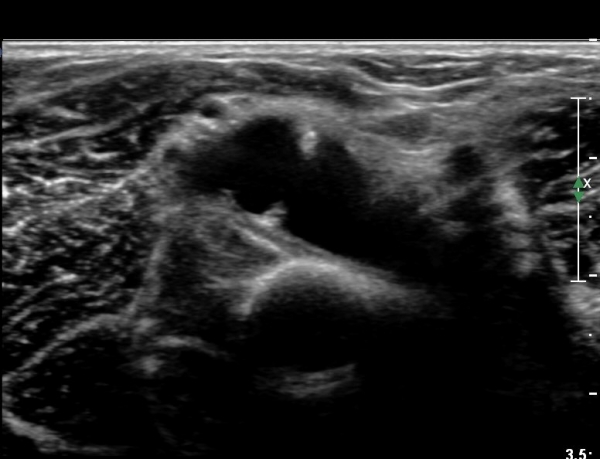

Èİñ°£ ½Å°æ Á¾´Ü¸é°Ë»ç¿¡¼­ ³¶Á¾¿¡ ÀÇÇÑ Èİñ°£ ½Å°æ ¾Ð¹Ú°ú  Èİñ°£ ½Å°æÀÇ ºÎÁ¾ÀÌ °üÂûµÈ´Ù(»çÁø 7).

out of plane À¸·Î ³¶Á¾ ÈíÀÎÀ» À§ÇØ ÁÖ»ç¹Ù´ÃÀÌ ³¶Á¾³»¿¡ À§Ä¡ÇÑ ¸ð½À(»çÁø 8)

³¶Á¾ ÈíÀÎ ÈÄ ³¶Á¾ÀÌ °ÅÀÇ º¸ÀÌÁö ¾Ê´Â ¸ð½À(»çÁø 9, 10)